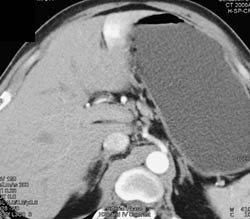

Central Cholangiocarcinoma With Dilated Common Bile Duct (CBD)